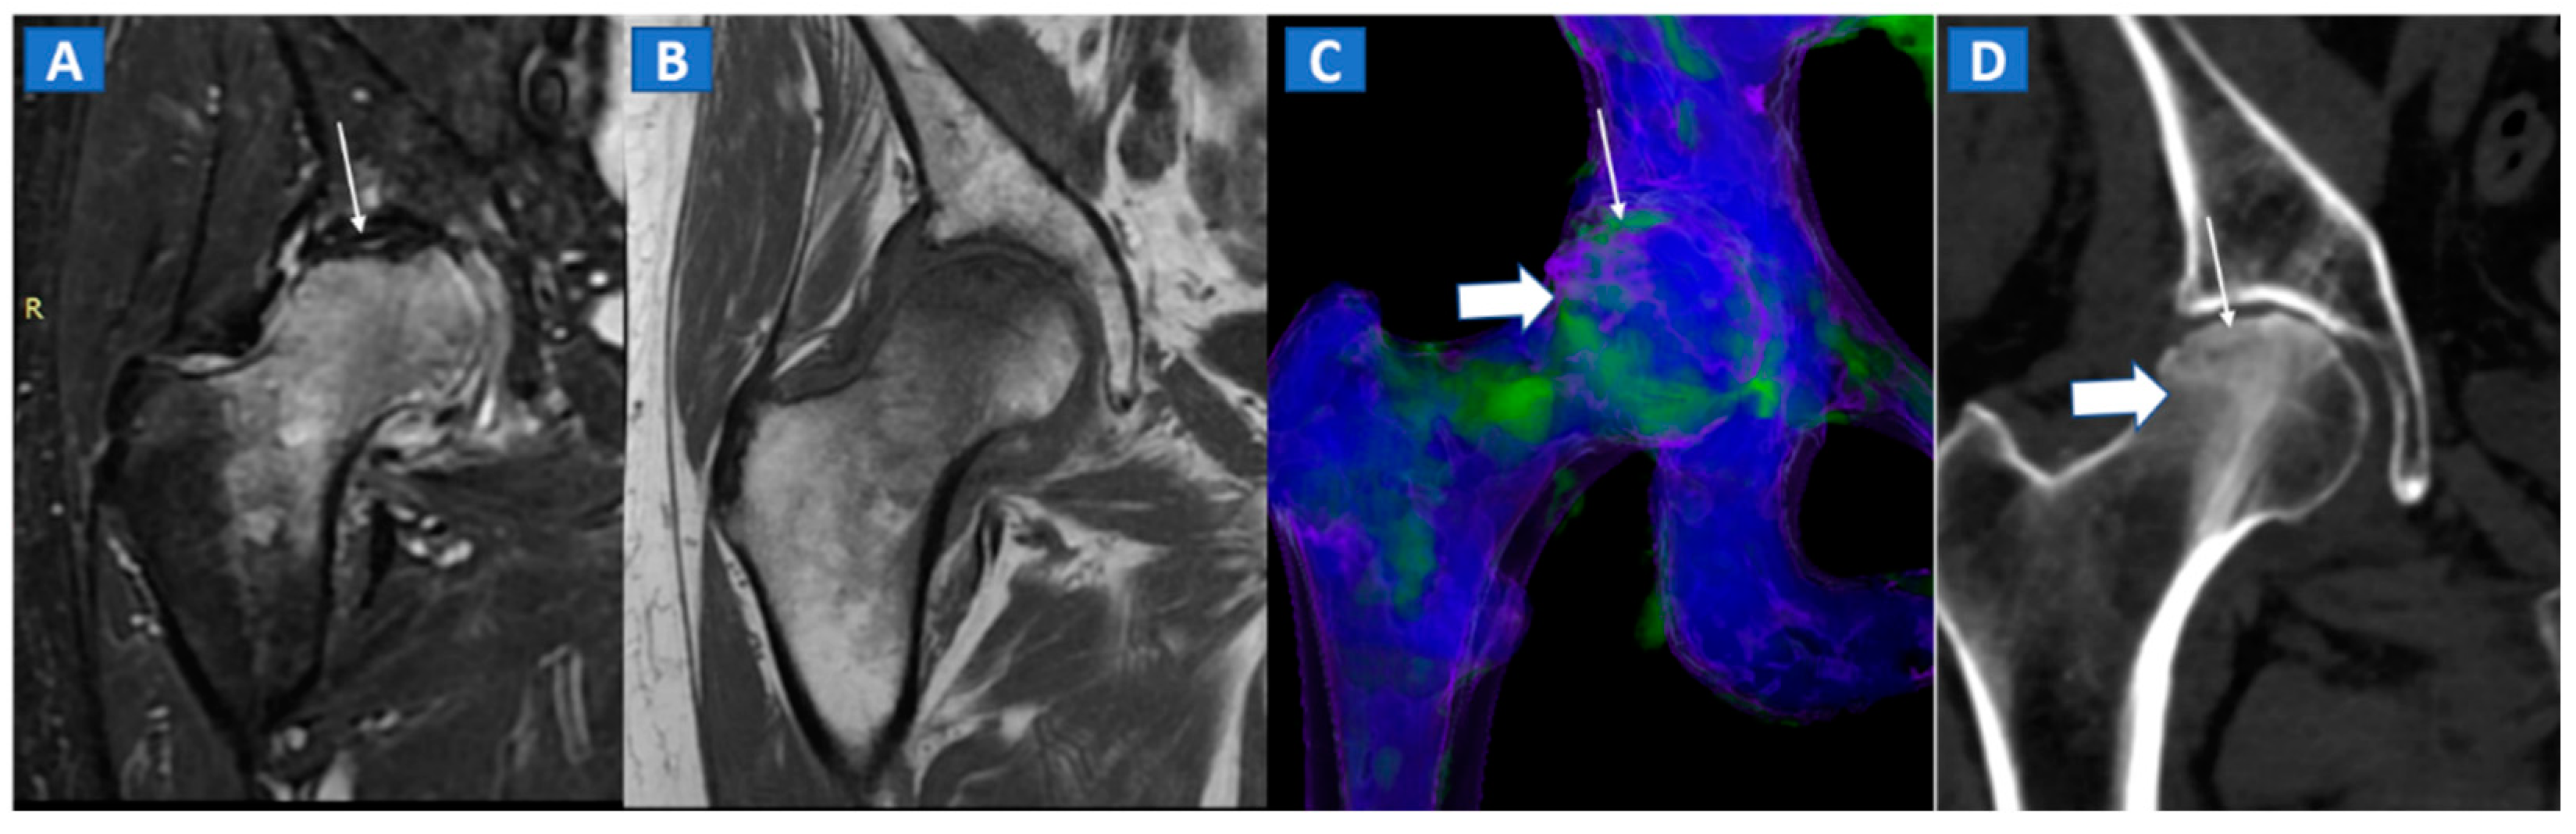

The diagnosis of osteonecrosis, defined as the ischemic death of bone, is based on the presence of a double line sign, BME, and subchondral fractures at MRI. With standard high-resolution CT images available (Figure 5), DECT can been used to identify BME and associated imaging findings, as well as to reliably diagnose AVN of the femoral head [9]. Importantly, DECT images can reliably identify subchondral fractures and cortical bone involvement, which are key in the prognosis and management of AVN of the femoral head (Figure 5). Thanks to high resolution images, DECT could be used for staging AVN, depicting for example cystic and sclerotic radiographic changes in early phases, or BME around sub-chondral collapsed areas. CT is also a highly reliable imaging tool in evaluating articular narrowing and calcific loose bodies.

A 58-year-old female with AVN of the right femoral head. On the coronal STIR MRI image (A), a hypointense serpiginous subchondral line, evident as a double line sign (arrow), is associated with diffuse BME involving the femoral neck and trochanteric region. On the corresponding T1-weighted image (B), hypointense BME seems to spare the medial aspect of the femoral head. On the DECT coronal 3D image (C), a flattened subchondral edematous area is depicted, with sclerosis-related artifacts hindering clear imaging of any BME of the head (thick arrow), although BME is apparent on the femoral neck. On the corresponding 1 mm coronal CT image with a soft-tissue window (D), it is possible to depict an increased density corresponding to the BME distribution (thick arrow), and a subtle subchondral hypodense line, which would be consistent with the diagnosis of a subchondral fracture (thin arrow). R = right.